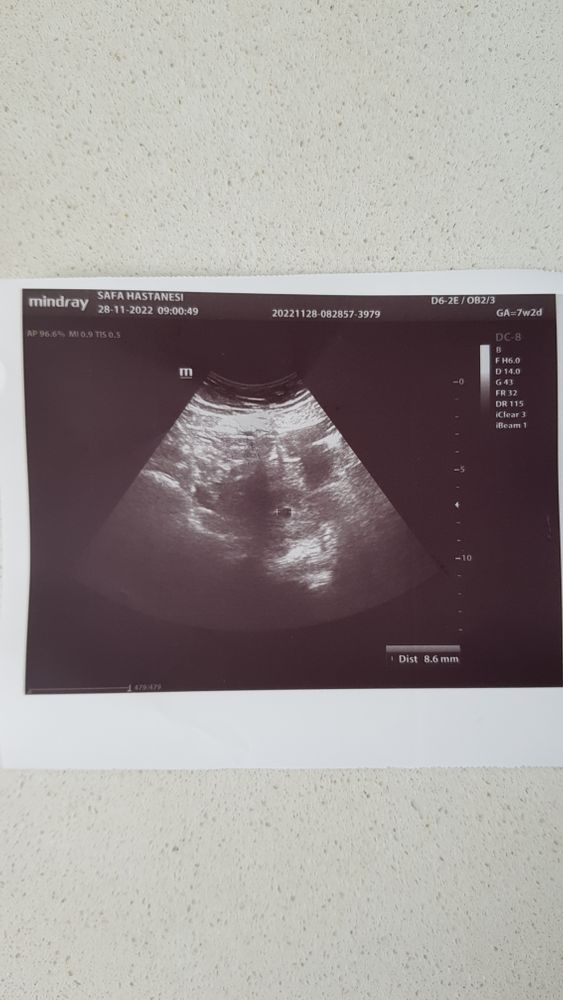

В апреле этого года была ЗБ,замер на сроке 6+1.Спустя 7 месяцев у нас снова получилось заБ🙏В 5+3 недельки сходила на УЗИ чтобы подтвердить Б-всё хорошо,увидели ПЯ,сказали прийти через 2 недели,чтобы послушать 💓.Я рада безмерно,но в то же время боюсь....меня переполняет страх,что опять всё повторится😭,опять услышать "нет сердцебиения"...Как успокоиться?Как не оглядываться на прошлое,а жить настоящим?🙄